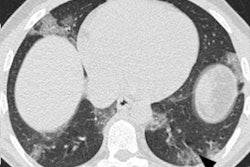

Readers rated chest CTs as "Surely COVID+," when patients presented with peripheral, bilateral, or multifocal ground-glass opacity (GGO) of rounded morphology and/or consolidation or crazy paving, reversed halo sign, or subpleural bands of consolidations. They classed scans as "Possible COVID+," when they had multifocal, diffuse, peripheral, or unilateral GGO and/or consolidation lacking a specific distribution or showed only few very small GGO with a nonrounded and nonperipheral distribution or when there were atypical findings, such as large pleural effusion, major lymph node size increase, or bronchiolitis pattern. Scans were deemed "COVID−" when the chest CT was normal or demonstrated another pathology.